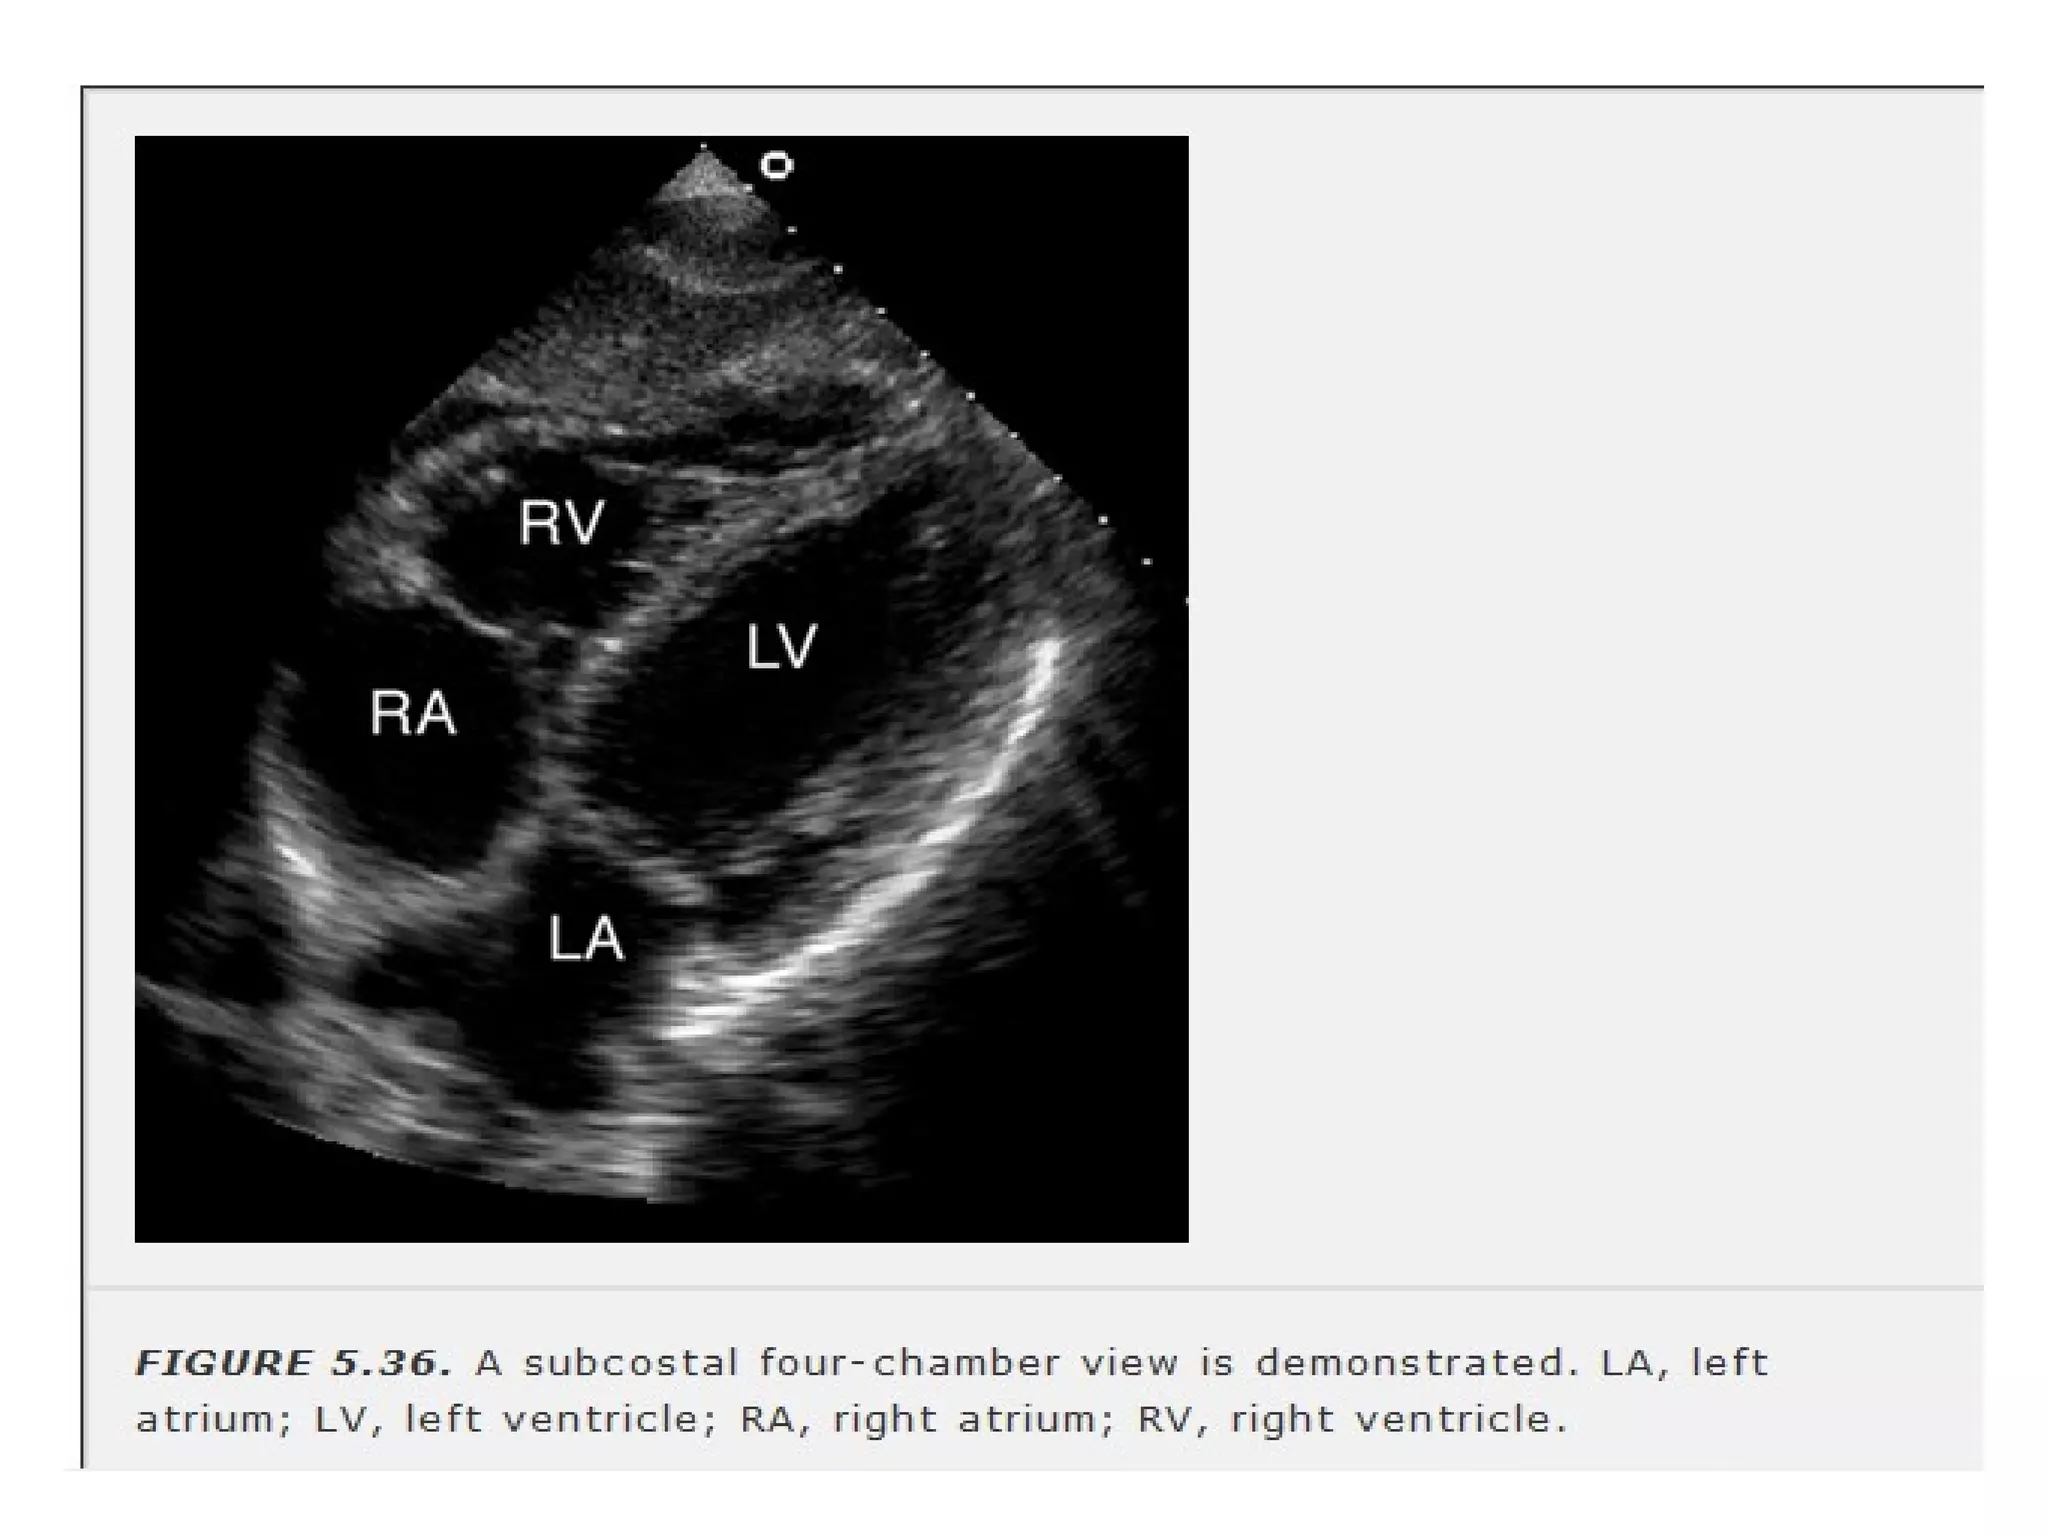

• 54.

• beam isoriented perpendicular to long axis of LV • better endocardial definition • septal defects are better delineated. • Only view that visualises superior portion of IAS • proximity of RV free wallto the transducer(pericardial tamponade) • IVC & hepatic veins are viewed.